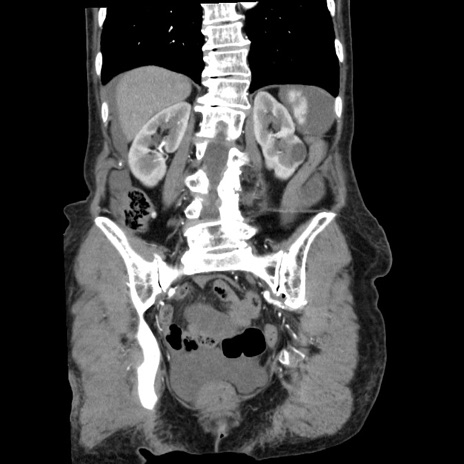

症例1(冠状断像)

【症例】80歳代女性

【主訴】腹痛

【現病歴】8時間前から腹痛あり来院。

【既往歴】糖尿病、脂質異常症、子宮体癌にて子宮全摘術

【身体所見】意識清明・会話良好だが腹痛で苦悶様、全腹部にわたって反跳痛と圧痛あり

【データ】WBC 13600、CRP 0.14、LDH 224、CK 90